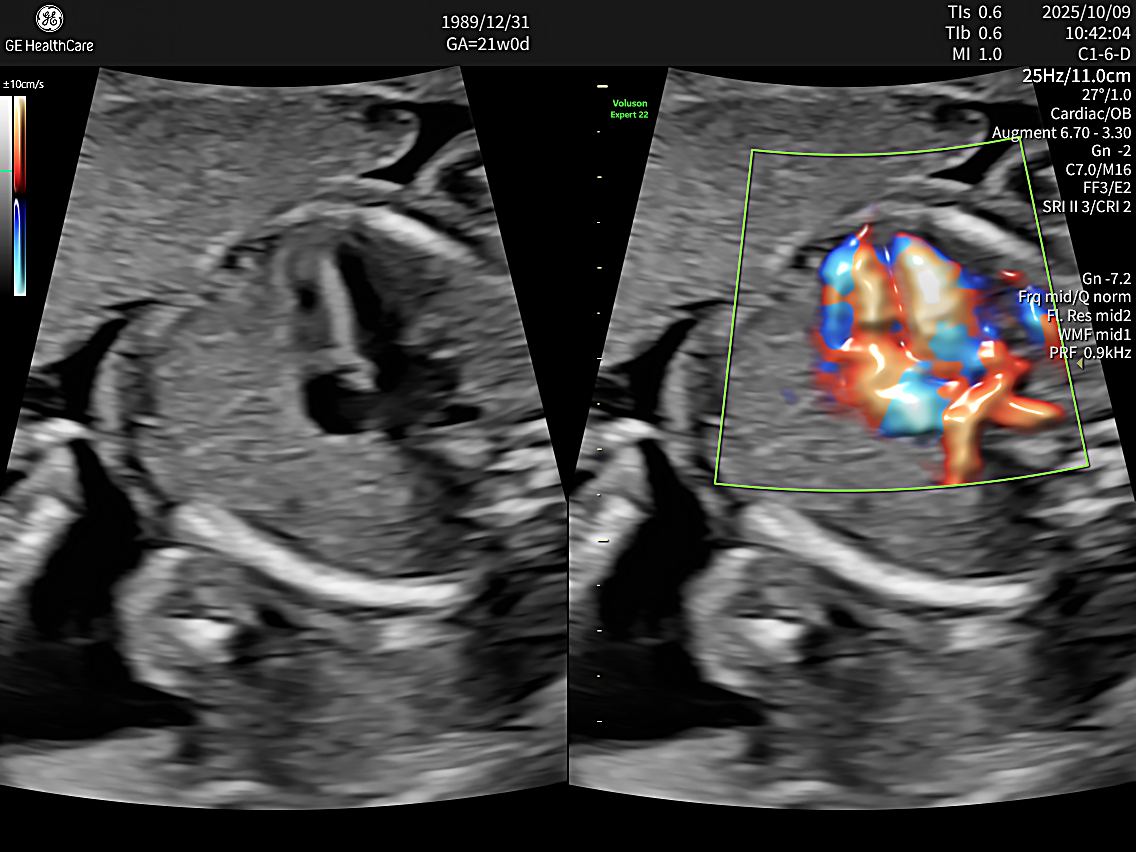

E22同時搭載多項高階影像技術,例如:高解析血流顯影技術,能清楚呈現胎盤與胎兒微小血管的血流狀態,幫助醫師更精準評估胎盤功能與胎兒循環狀況。

同時,系統也具備即時3D與4D胎兒超音波成像能力,能清楚呈現寶寶臉部輪廓與動態表情,例如:打呵欠、吸手指或微笑等畫面,讓準爸媽在進行胎兒4d超音波時,也能留下更清晰立體的珍貴影像。

在檢查應用上,E22 可支援多種產科與婦科檢查,包括一般產檢2D影像、3D立體影像、4D超音波以及胎兒結構評估等。透過高解析影像與智慧化輔助判讀功能,醫師能更有效率完成胎兒生長測量、器官結構評估與血流分析,提升整體檢查準確度。